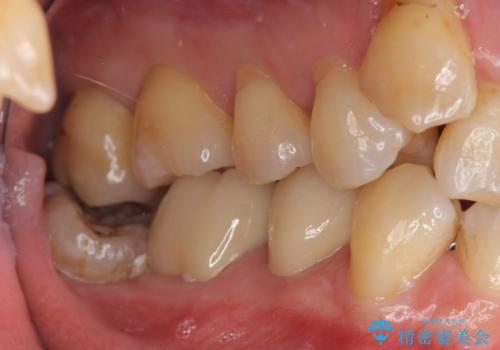

詰め物の下が虫歯 つぎはぎの歯をしっかり治療